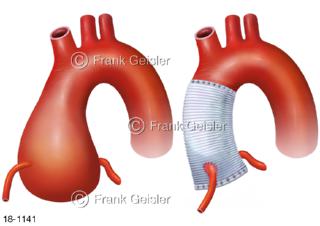

18-1141 Aorta Aortenbulbus, Aortenwurzelerweiterung und Aortenersatz Gefäßstütze Stent